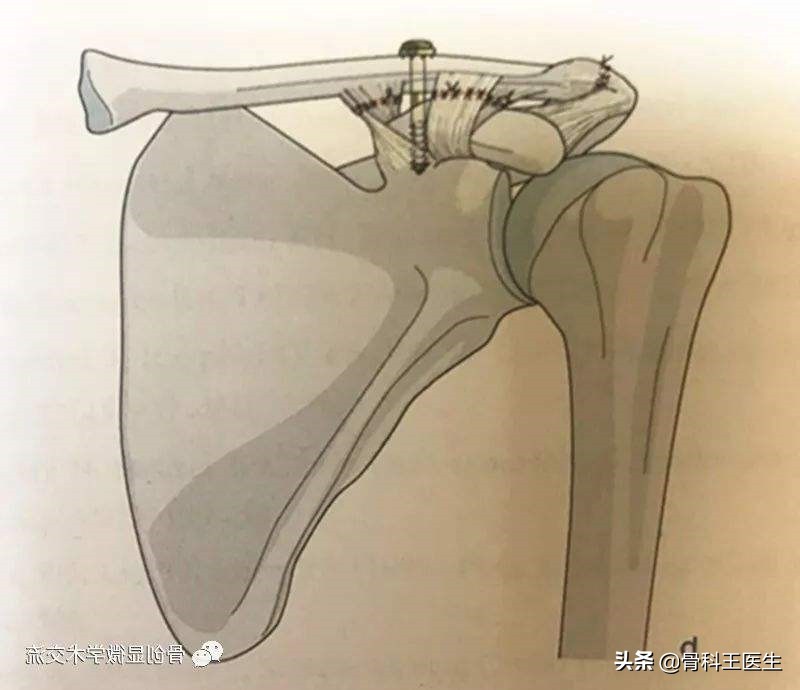

3、也可以把韧带缝起来以后上个螺钉固定下就行了。